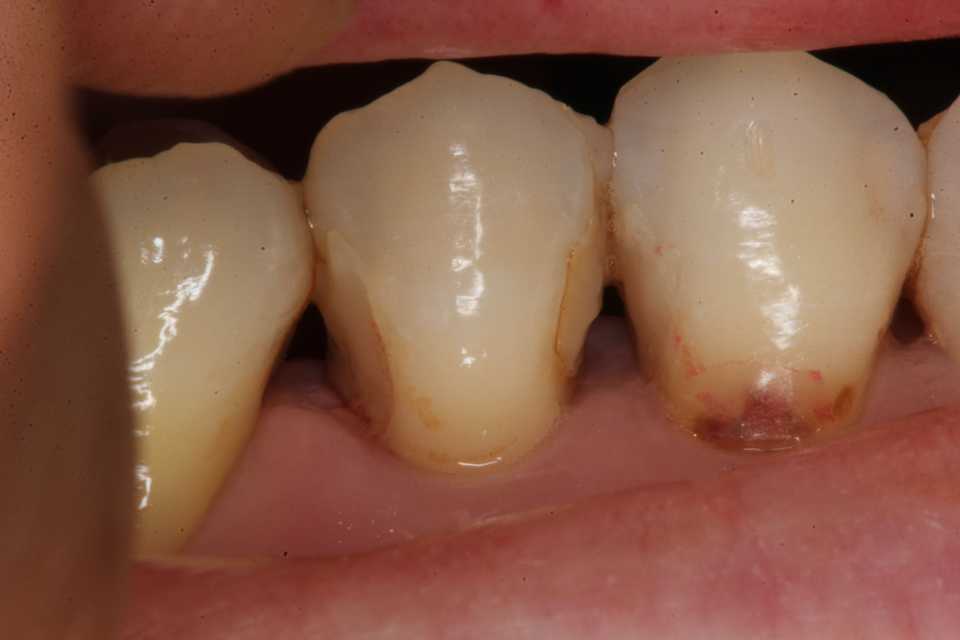

15歳男子、上顎前突観が気になる。出っ歯が気になるのでどうにかならないか?という主訴だったのだが、上下顎の歯列狭窄が見られる。いわゆるディープバイトとはちょっと違うかもしれないが、治療法は基本同じというということでアップしてみたい。ディープバイトは見かけ上の分類に過ぎず、その原因は経験上、強過ぎる咬合力による臼歯部の圧下、咀嚼筋群、口輪筋の過緊張による前歯部の後方傾斜、うつ伏せ寝、横向き寝等の態癖による歯列の狭窄で、それらに伴う下顎後退が特徴的に見られる。この子の場合はうつ伏せ寝により上顎歯列の狭窄(横幅が狭い)し、それに伴い前歯部が外側に弾かれて出っ歯に見える。それだけではなく、噛み締めによる下顎の臼歯部の低位、下唇を噛む等の習癖もあるかもしれない。治療方針は上顎歯列を拡大床装置により拡大しつつ、仰向けで寝るようにして、なるべく前の方で噛んでね。と指示するだけだ。最近は体力の低下でフルブラケット矯正が億劫になってきたので、お金も欲しくないし、なるべく簡単でコストが掛からない方法を考えて実践している。早く綺麗に治そうと思えば最低でも下顎はフルブラケットした方が良いかもしれないが、コストは20倍だ。前回の症例参照。直近の画像は撮るのを忘れたが、だいぶ良くなっている。では時系列でどうぞ寝相等の態癖による典型的な歯列狭窄だ。歯学部では西洋ベル型の歯列と習うが、うつ伏せ寝によってこうなるとは習わない。2ヶ月後